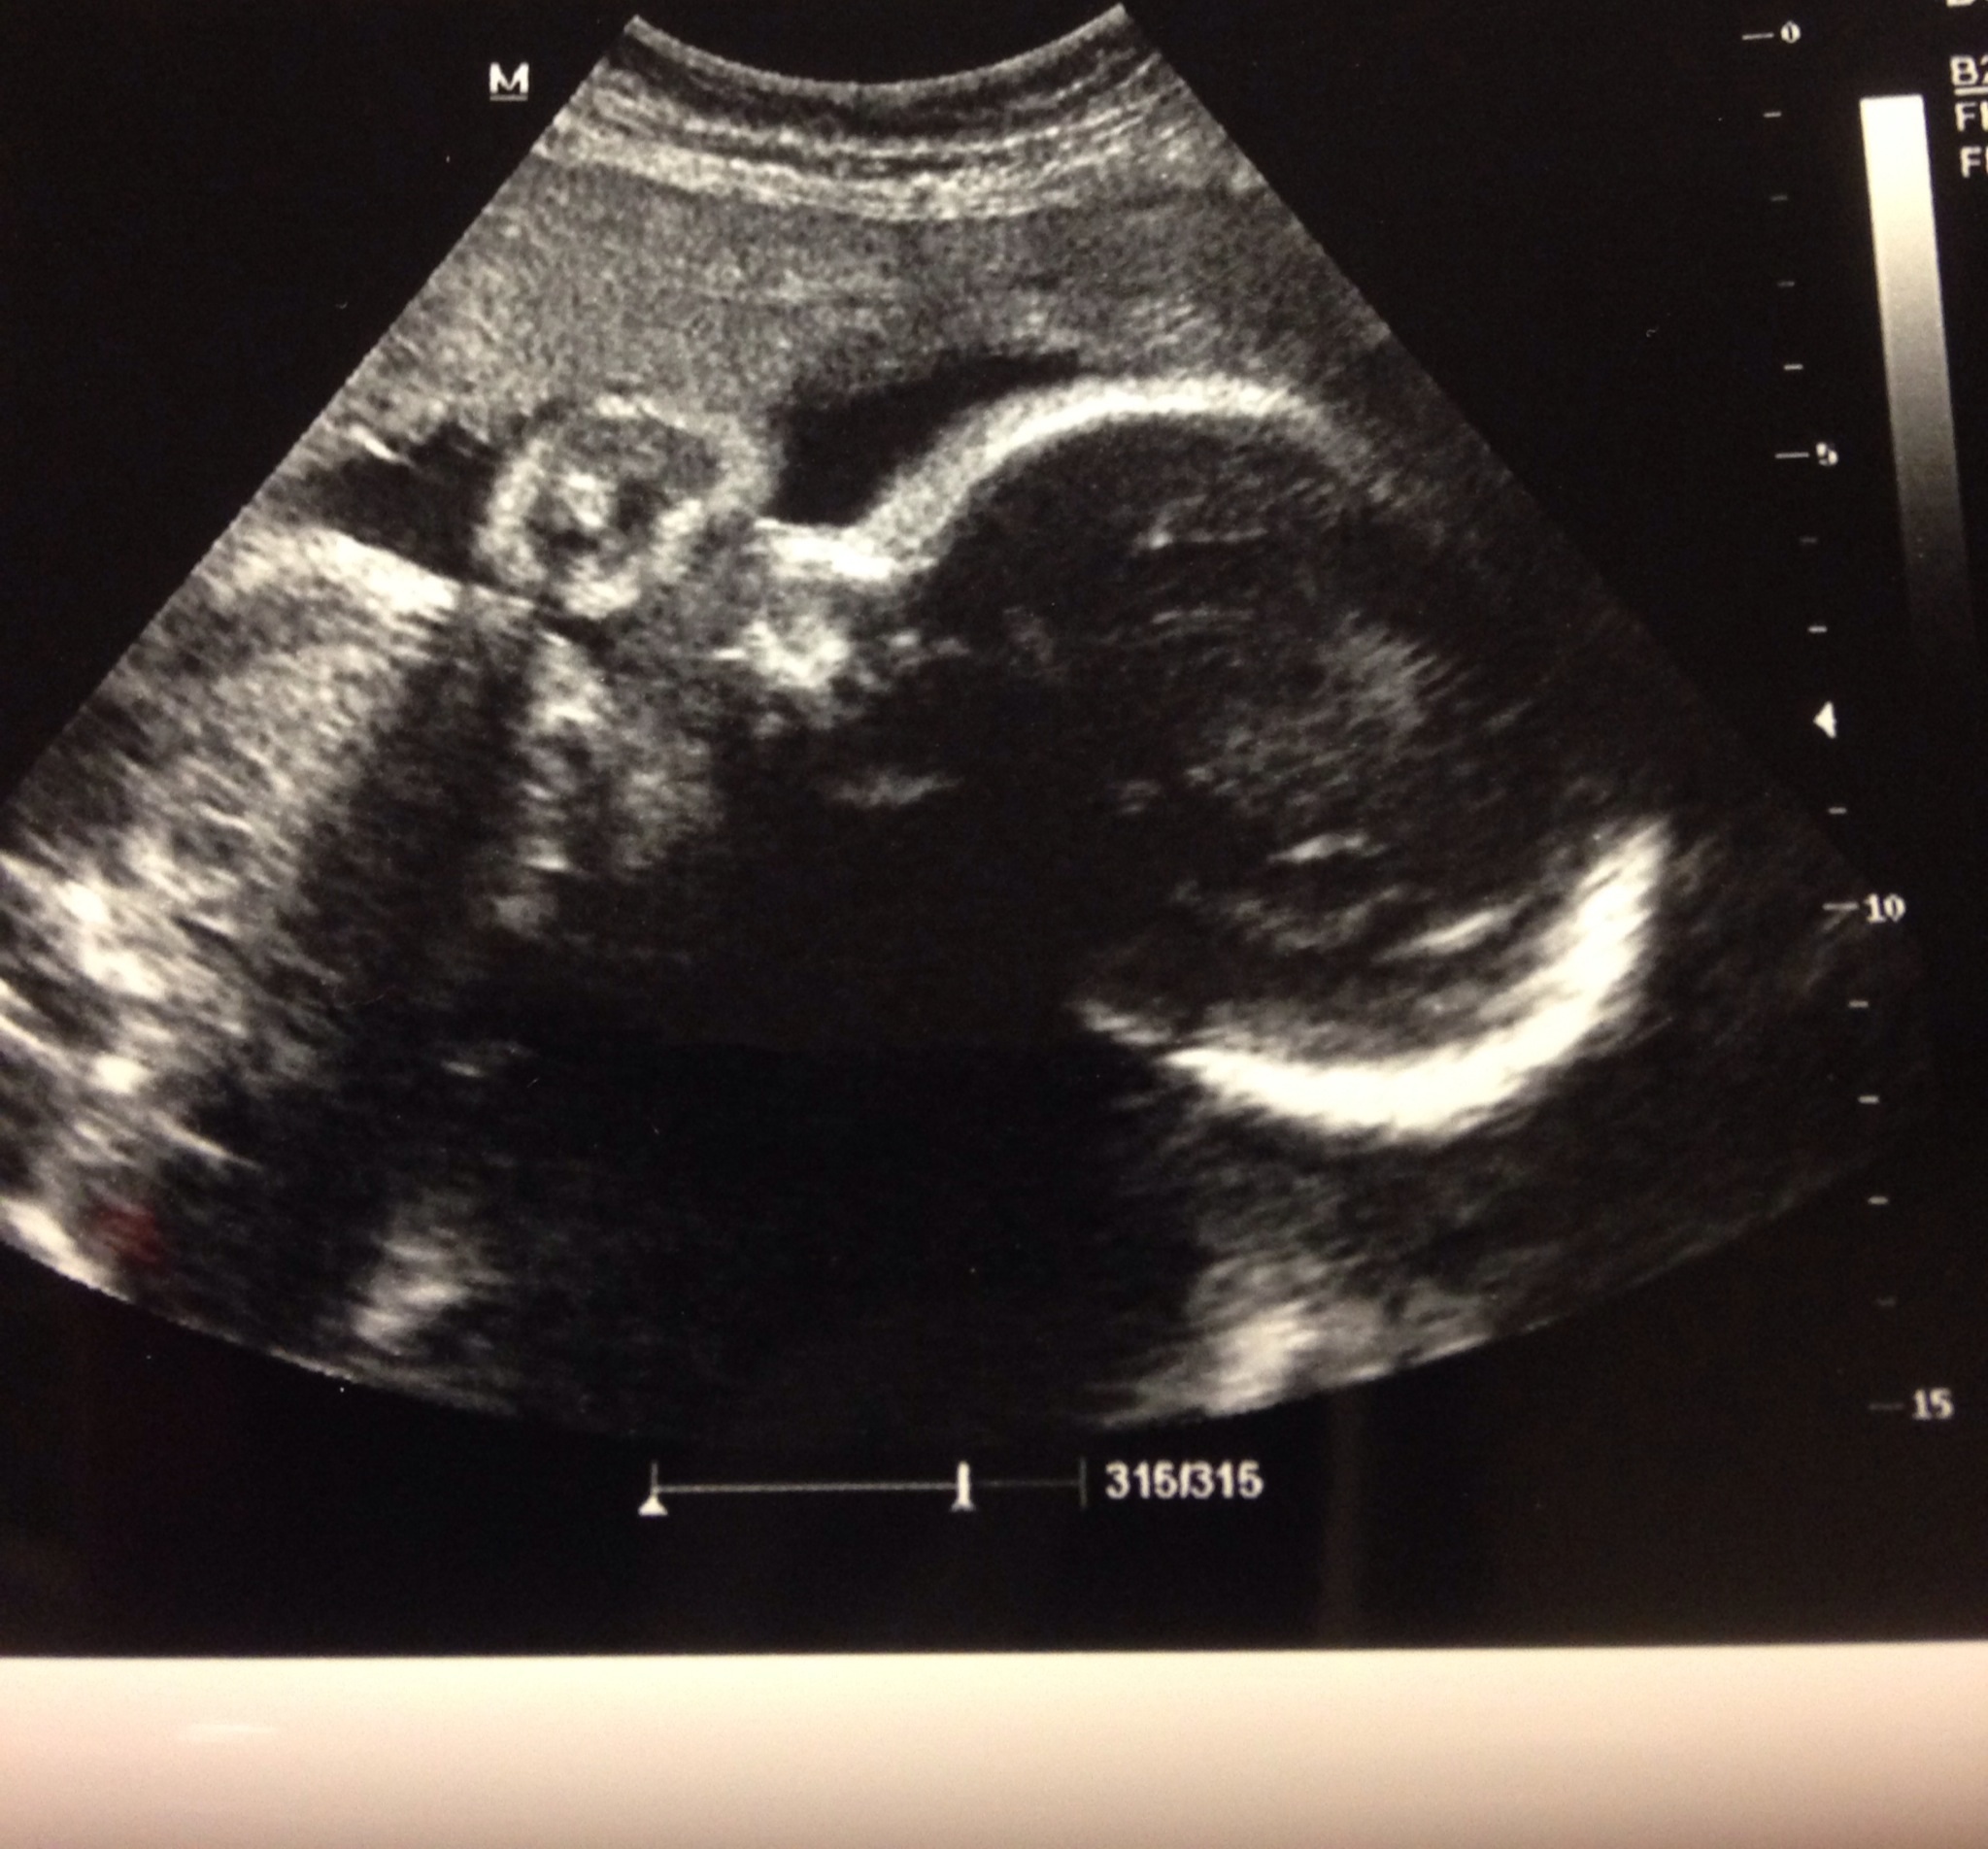

Is it me or does my baby's head look big? I had a ultrasound today to double check my fluid, while i was waiting for my 3 hour test I had a 3D ultrasound but the tech couldn't get any good pics bc I had low fluid, so I had another normal ultrasound to check fluid level, the level came back at 9 which was normal so I must of been bc I had to fast and not drinking fluids.

• Forgot to add picture

• I'm sure everything is fine. Sometimes the angle looks weird. I have one ultrasound pic where his head looks huge, too. I'm not worried.

• Nah I'm sure it is fine. My little one looked like his nose was HUGE. We got a little nervous so she showed us in 3d and it was fine. I'm sure it is just a shadow or the angle.

• It's probably just the angle I wouldn't worry unless the Dr says something. My baby's head and body have measured in the 90% at my scans too. Good luck!

• I think it looks big. But I also think my kid's head looks huge. And, in general, think most babies' heads look huge.

• Babies have giant heads. I'd be more worried about one that actually looked proportionate to its body. Only your OB and US tech can tell you if the specific measurements are a concern.